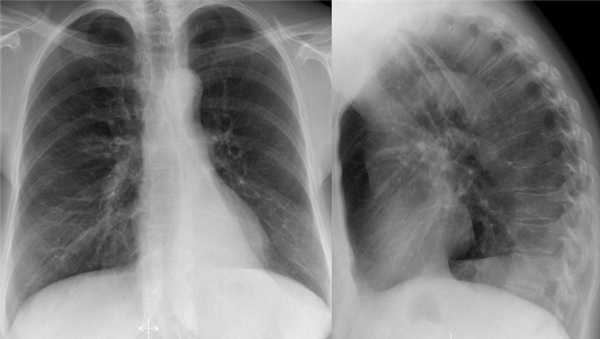

- Минимальное уменьшение объема легкого без подъема левого купола диафрагма.

- В загрудинном пространстве визуализируются изменения высокой плотности, которые спавшейся верхней доли левого легкого.

- Корень левого легкого патологичен, что может соответствовать образованию, обтурирующее просвет бронха.

- Выше перечисленные находки наводят на мысль, что это ателектаз верхней доли левого легкого.

На КТ снимках синей стрелкой указан долевой ателектаз, а красной стрелкой опухоль, которая обтурирует левый верхний долевой бронх (центральный рак легкого.

Ателектаз верхней доли левого легкого с типичным симптомом воздушного серпа (Luftsichel sign — luft(air)+sichel(sickle)), обусловленный гипервентиляцией верхнего сегмента нижней доли левого легкого на фоне коллапса верхний доли левого легкого. Гипервентилируемый

сегмент визуализируется на прямой рентгенограмме от дуги аорты до апикальной части легкого.